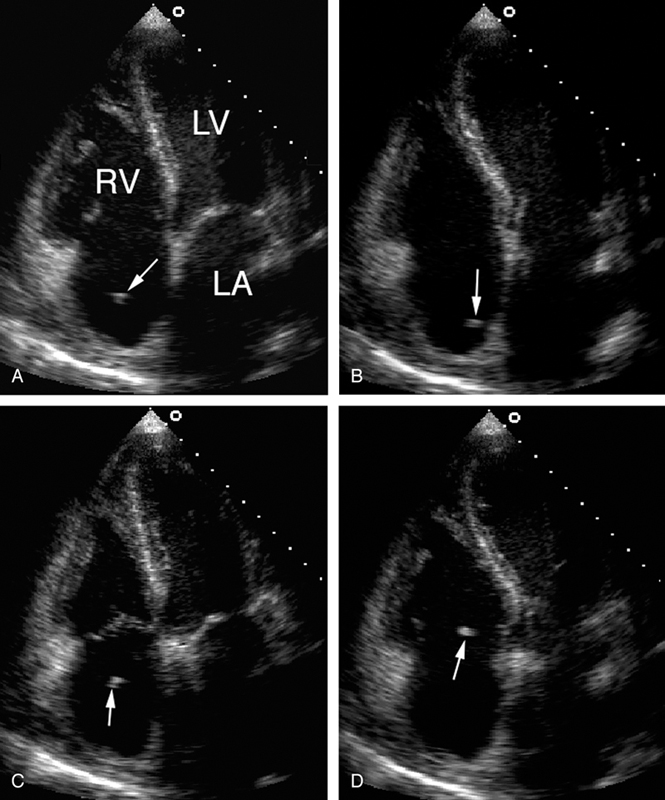

فحوصات تشخيصية لبعض امراض القلب والشرايين التاجية